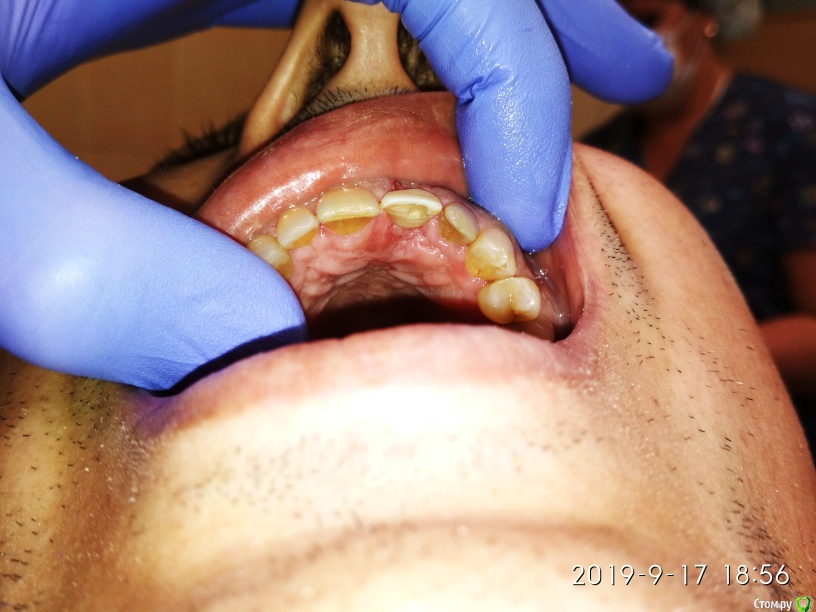

Дмитрий М Опубликовано 25 сентября, 2019 Поделиться Опубликовано 25 сентября, 2019 Пуциент 43г. перелом 21 зуба пациент без эстетических притязаний, совсем. главное, чтобы было дешево )))воксап- удаление - щит- имплантация- изготовление временной- фиксация Ссылка на комментарий